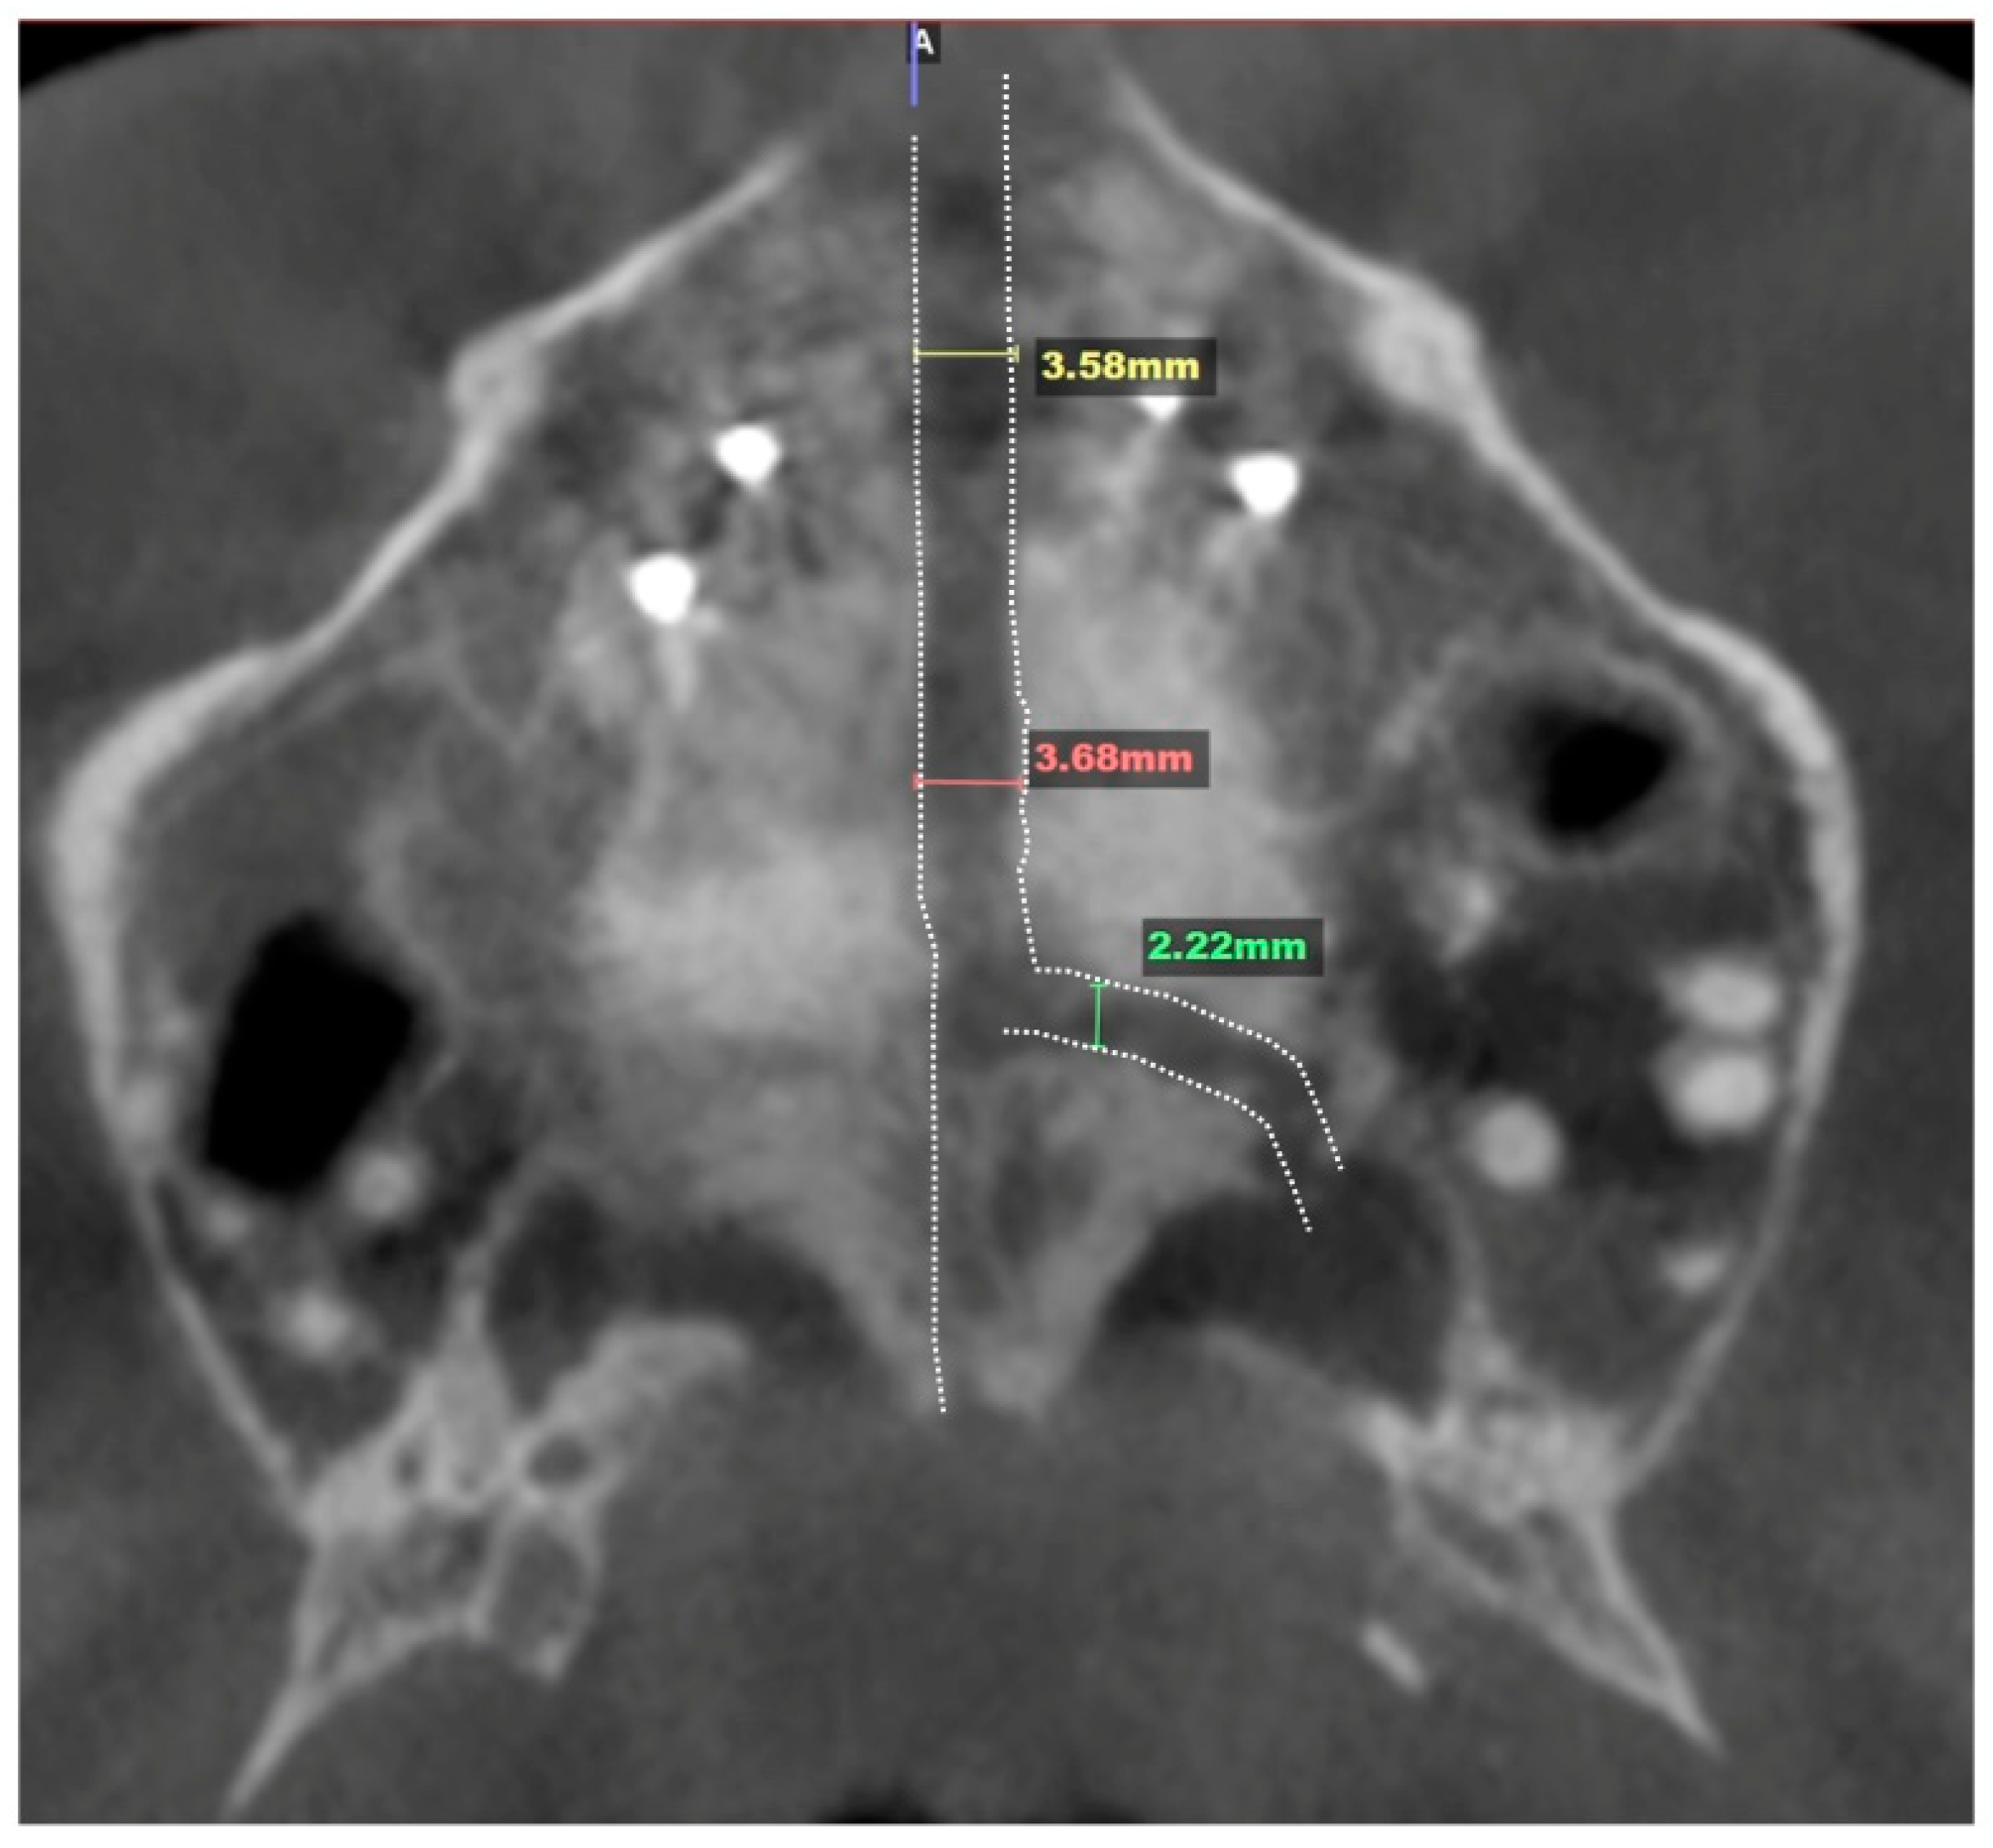

2.3.2. Design of 3D Surgical Guide

2.3.3. Osteotomy Planning and Appliance Design

2.3.4. Postoperative Assessment, Outcome Analysis, and Asymmetry Correction